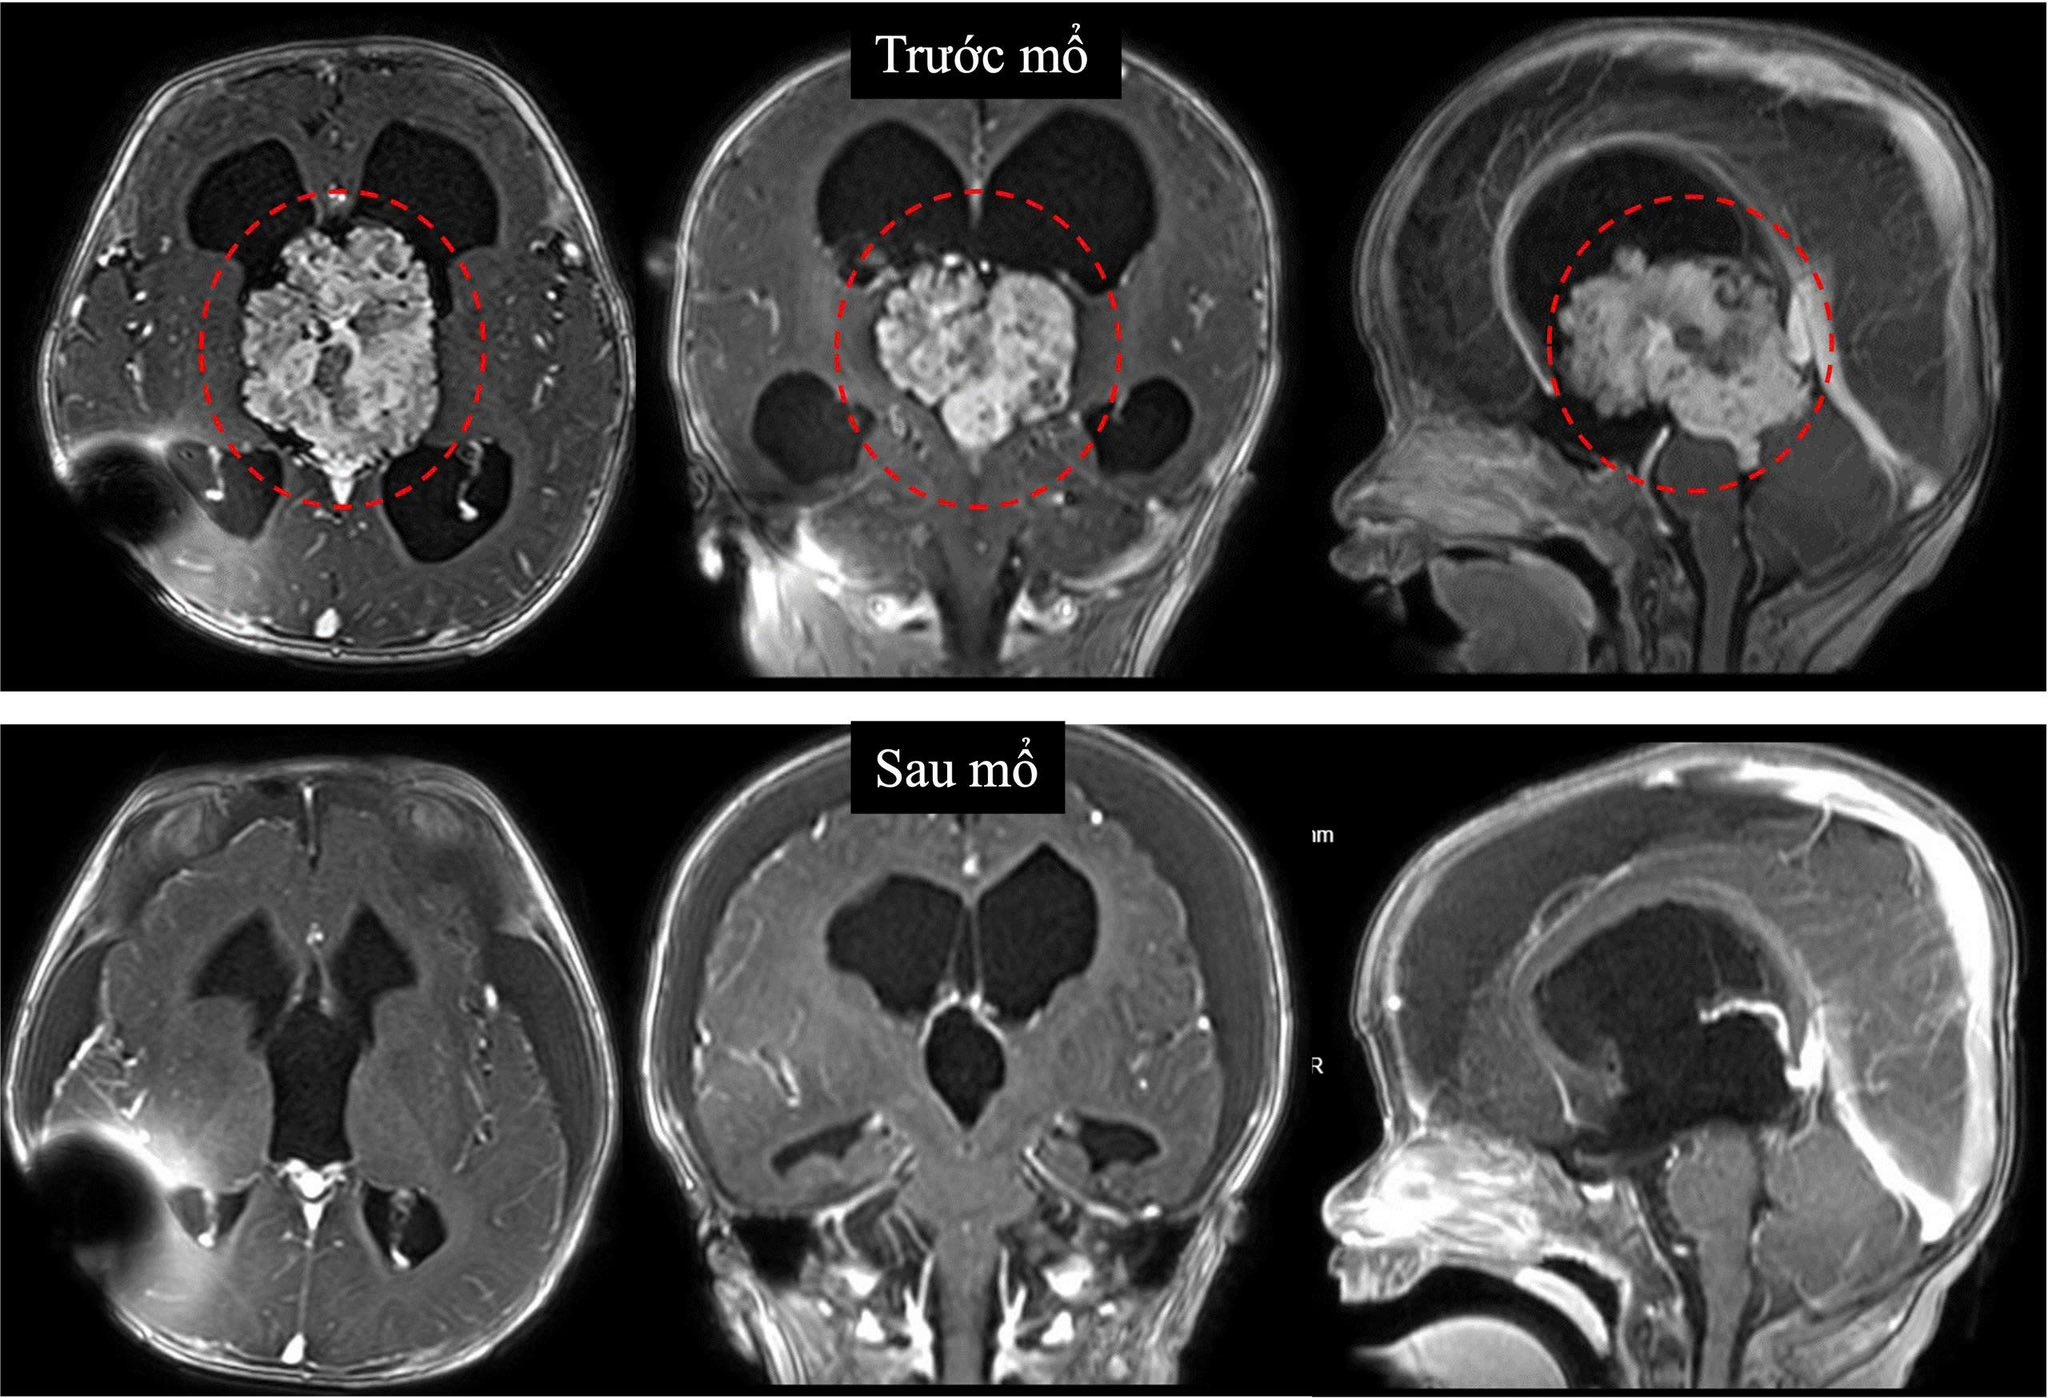

Kết quả siêu âm qua thóp và chụp cộng hưởng từ xác định khối u nằm ở não thất III, gây chèn ép dẫn đến não úng thủy tắc nghẽn nặng. Đây là vị trí sâu trong não, tập trung nhiều cấu trúc thần kinh và mạch máu quan trọng, khiến việc phẫu thuật tiềm ẩn nguy cơ cao.

Trước đó, do bệnh nhi còn quá nhỏ, các bác sĩ đã đặt dẫn lưu não thất - ổ bụng vào cuối tháng 11/2025 nhằm giảm áp lực nội sọ tạm thời và theo dõi thêm. Tuy nhiên, sau 3 tháng, khối u phát triển nhanh, tăng kích thước hơn 3 lần, buộc ê-kíp phải chỉ định phẫu thuật sớm.

Ca mổ được tiến hành ngày 25/3 với sự phối hợp của nhiều chuyên khoa như Ngoại thần kinh, Gây mê hồi sức và Hồi sức ngoại. Sau 6 giờ phẫu thuật căng thẳng, ê-kíp đã bóc tách thành công khối u kích thước khoảng 6 cm.

Hình ảnh khối u trước và sau mổ. Ảnh: BVCC.

Theo TS.BS Trần Minh Huy, khoa Ngoại thần kinh, đây là ca mổ đặc biệt khó do khối u nằm sâu ở trung tâm não, có nhiều mạch máu nuôi, trong khi bệnh nhi còn nhỏ, nguy cơ mất máu cao. Quá trình phẫu thuật đòi hỏi sự chính xác và phối hợp chặt chẽ giữa các chuyên khoa để đảm bảo an toàn tối đa.